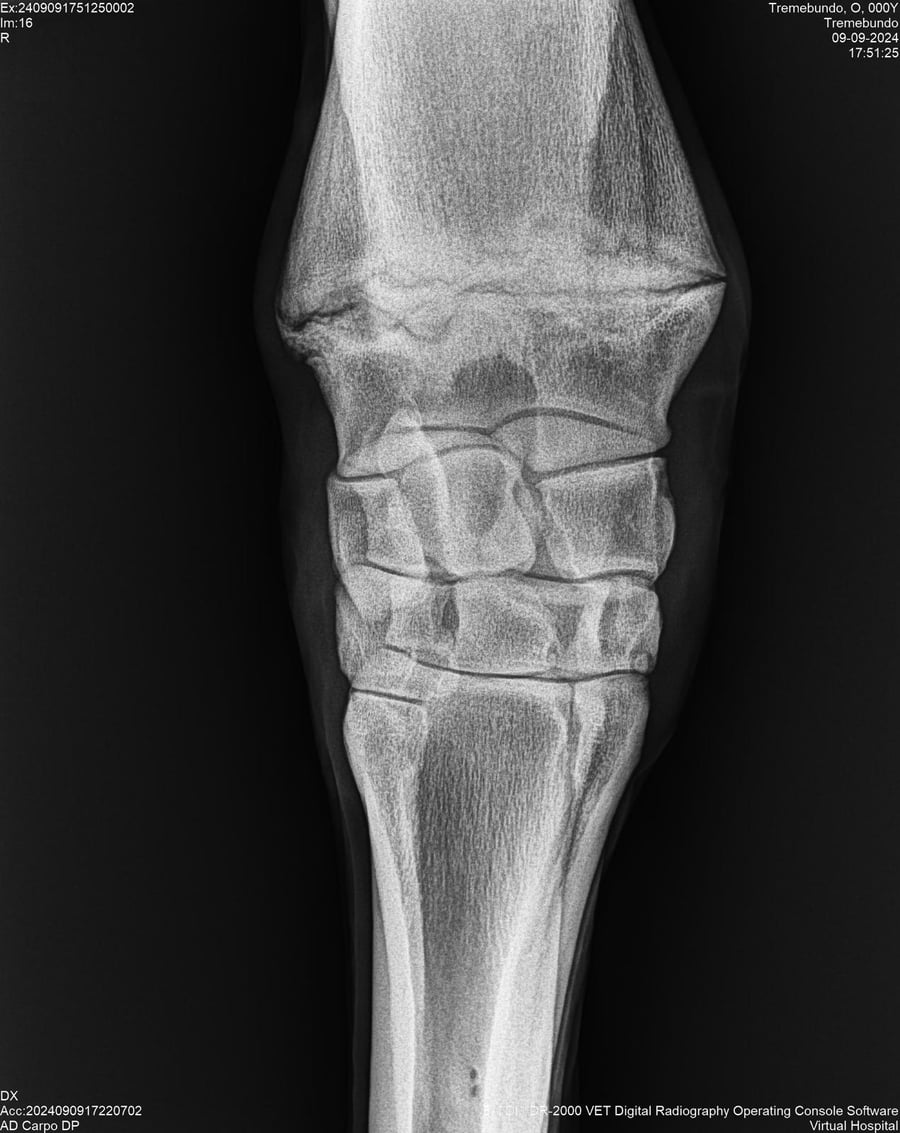

LOTE 37, TREMEBUNDO

Ficha del Lote

Identificador: #291140-

Generacion 2022